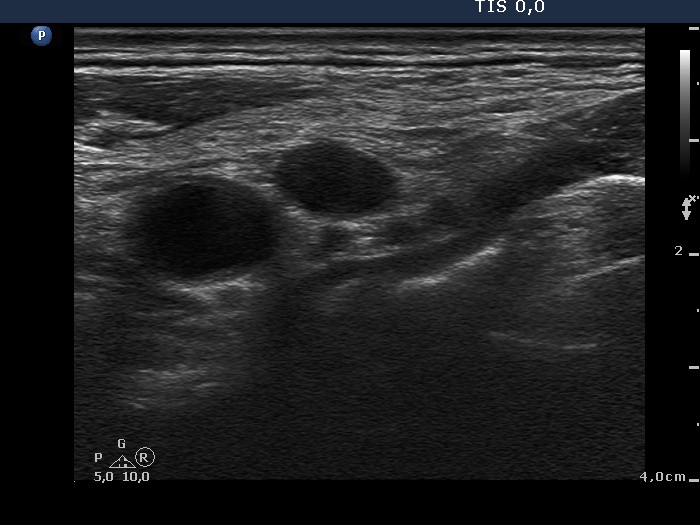

Ultrasonography: the thyroid was intact. There were multiple nodes in both supraclavicular regions. The nodes presented an absolutely irregular shape and border. They contained numerous hyperechogenic circumscribed areas.